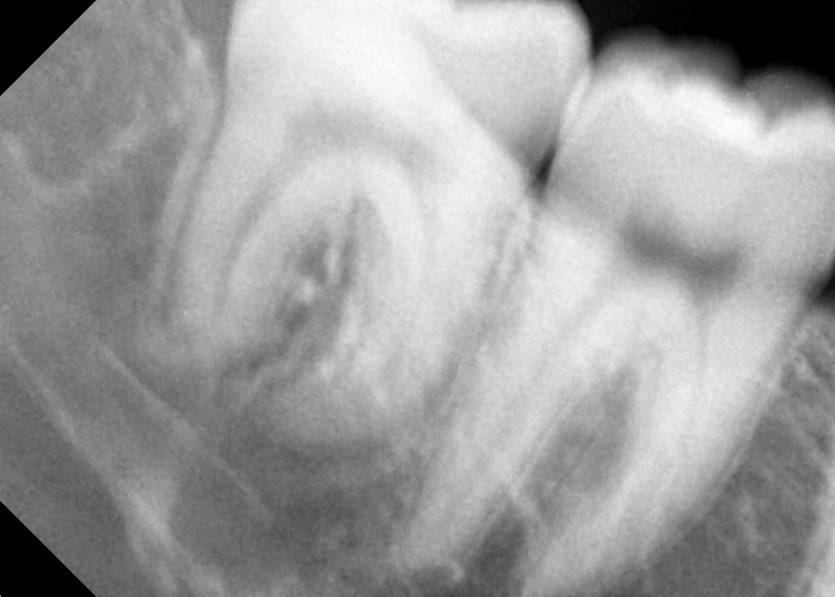

#18,48 사랑니 발치

#48 사랑니 발치

구강외과 전문의가 당일 발치했습니다.